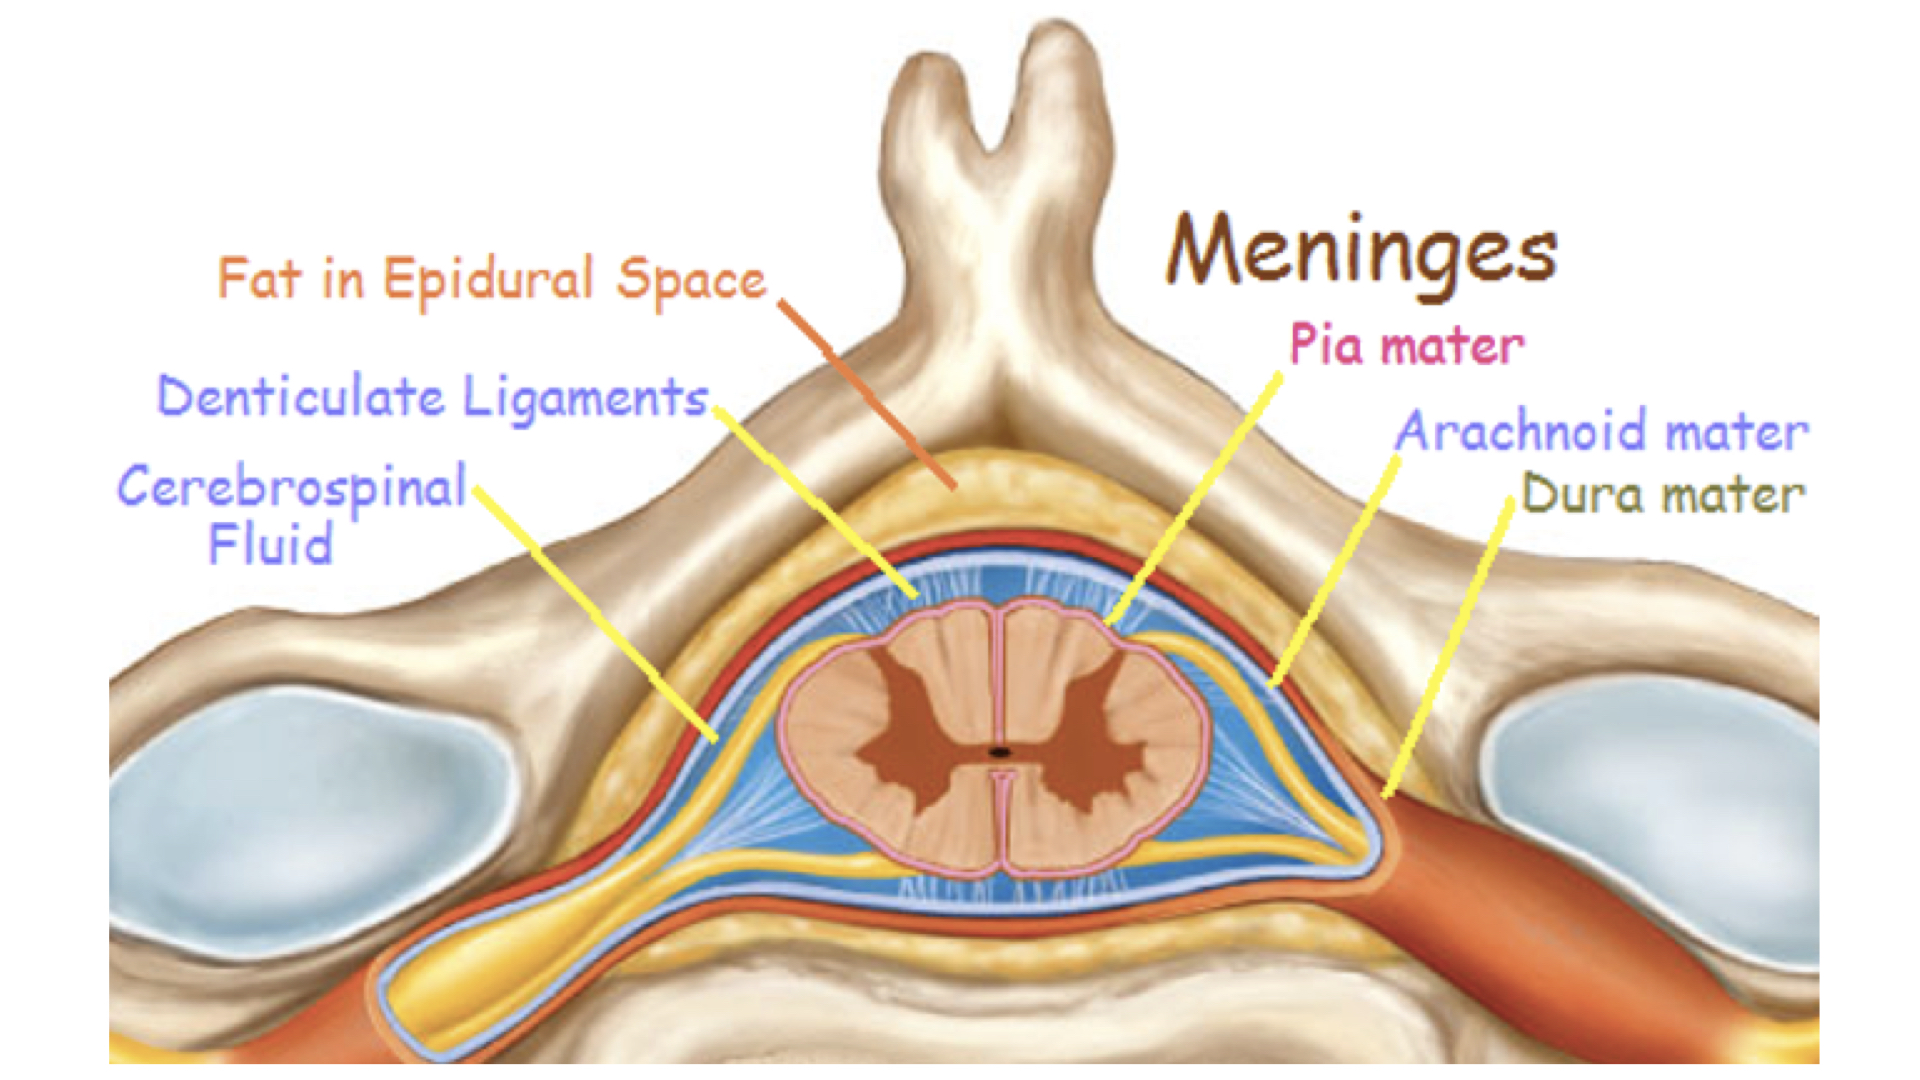

2. Covered with meninges - protective layers, prevent movement/shock

a. Dura Mater- “tough mother” dense connective tissue, covers spinal nerves to the intervertebral foramen, continuous with periosteum of the bone, creates on functional unit

b. Arachnoid – spider web, delicate connective tissue

c. Pia Mater – “delicate mother” – adheres to the surface of the brain and the spinal cord, can’t be removed. Contains many blood vessels for nourishment

d. Spaces

1. epidural – between the dura mater & vertebral column, contains blood vessels, adipose & loose connective tissue (provides padding around cord)

a. Epidural Block – anesthetic injected into the epidural space, affects only spinal nerves in immediate area, relieves pain

2. subarachnoid – space between the arachnoid and pia mater, filled with cerebrospinal fluid (CSF).

5. Denticulate Ligaments- help to hold the spinal cord in place, interweave with the periosteum of the bones